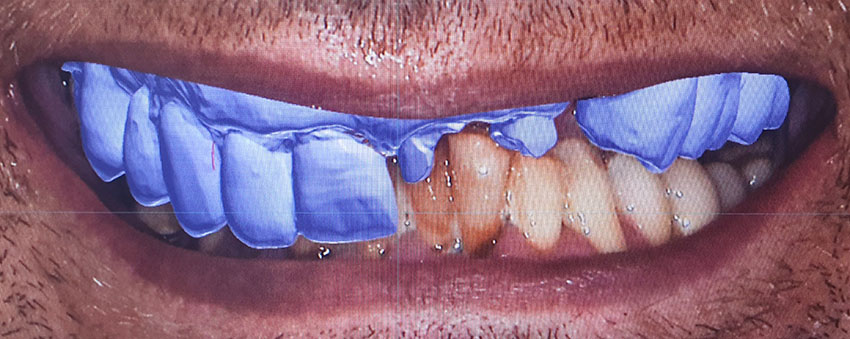

L’utilizzo di software di progettazione permettono di coinvolgere il paziente dall’inizio nelle fasi di progettazione, così da poter scegliere la migliore estetica possibile per riabilitare il suo caso.

Successivamente inizierà la fase di progettazione, dove un programma dedicato elaborerà tutti i dati acquisiti. Inoltre verra’ coinvolto il Tecnico, che svilupperà il progetto Protesico definitivo, da sottoporre ad approvazione del paziente prima dell’intervento

Dopo aver stabilito la nuova estetica del paziente, verranno progettati gli impianti e successivamente la dima chirurgica.